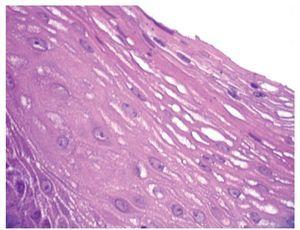

Se presenta el caso de un hombre de 45 años de edad que acudió a consulta por presentar pirosis y regurgitaciones de cinco años de evolución con respuesta parcial al consumo de inhibidores de la bomba de protones (20 mg a 40 mg de omeprazol en terapia a demanda). Por la cronicidad de los síntomas se le realizó una endoscopía del tracto digestivo superior en donde se encontró en el tercio medio del esófago una lesión exofítica de aspecto vegetante, con bordes bien delimitados y de color rosa blanquecino que midió aproximadamente 1 cm de longitud (Figura 1). Ante la sospecha de lesión papilomatosa asociada a virus del papiloma humano (VPH) se realizó biopsia excisional y se envió a estudio anatomopatológico. El resto del estudio endoscópico mostró esofagitis erosiva grado A de Los Angeles. Se prescribió tratamiento con omeprazol 20 mg dos veces al día por seis semanas. Por histología, la lesión presentó epitelio plano estratificado maduro con acantosis y papilomatosis (Figura 2), con centros fibrovasculares (Figura 3) dando un aspecto digitiforme. Las células basales eran grandes pero sin atipias nucleares, en los estratos superficial y medio las células mostraron maduración (Figura 4). Se realizó tinción de inmunohistoquímica para búsqueda de VPH la cual fue negativa (Figura 5). En el seguimiento se realizó endoscopía a los seis meses sin evidencia de recidiva de la lesión.

¿ Figura 2. Epitelio plano estratificado maduro, con acantosis y papilomatosis; poco aumento.